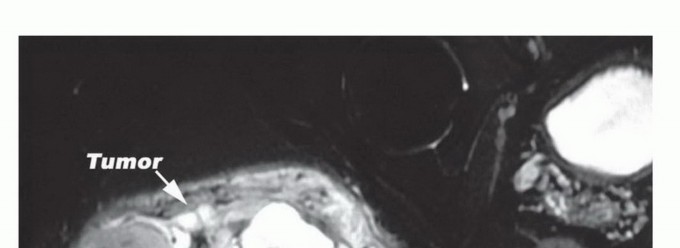

الشكل 1: يوضح هذا التصوير بالرنين المغناطيسي (صورة T1 كورونال) ساركوما كبيرة في الأرداف تمتد عبر الثلمة الوركية وتضغط على العصب الوركي. ينشأ العصب الوركي من الجزء السفلي من العمود الفقري، ويمر إلى جزء الحرقفة من الحوض، ويخرج عبر الثلمة الوركية، ويمر أسفل العضلة الكمثرية. تظهر الصورة تورمًا في العضلة الألوية الكبرى. تميل أورام الأرداف إلى النمو على طول مسار المقاومة الأقل، ويمكن أن تمتد عبر الثلمة الوركية وإلى الحوض. يمكن أن تمتد أيضًا بشكل بعيد إلى الفخذ وتغزو جناح الحرقفة. من الصعب تحديد مدى تغلغل الورم في العصب الوركي بشكل كامل، ولكن العصب الوركي نادرًا ما يتأثر بالورم الفعلي وعادة ما يتم ضغطه وإزاحته بواسطة كبسولة الورم أو كبسولته الكاذبة.